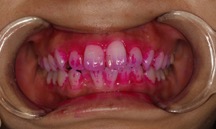

PCRは、歯垢に反応する着色液を使用して、日常の歯磨きで磨き残された部分を染め出す方法です。この技術を用いることで、普段の歯磨きで磨けていない箇所が明確になり、より効果的なブラッシング方法を学ぶことができます。